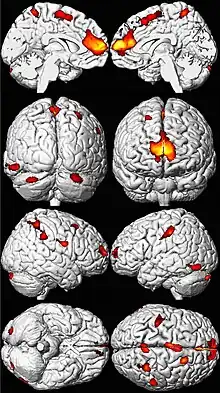

.png.webp)

Lead poisoning can cause a variety of symptoms and signs which vary depending on the individual and the duration of lead exposure.[27][28] Symptoms are nonspecific and may be subtle, and someone with elevated lead levels may have no symptoms.[29] Symptoms usually develop over weeks to months as lead builds up in the body during a chronic exposure, but acute symptoms from brief, intense exposures also occur.[30] Symptoms from exposure to organic lead, which is probably more toxic than inorganic lead due to its lipid solubility, occur rapidly.[31] Poisoning by organic lead compounds has symptoms predominantly in the central nervous system, such as insomnia, delirium, cognitive deficits, tremor, hallucinations, and convulsions.[26]